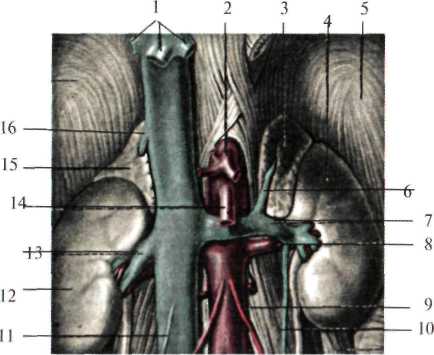

Надпочечники (gl. suprarenales)

Парные железы внутренней секреции, расположены на уровне X-XI грудных позвонков, у верхних полюсов почки, заключены в фасциальные ложа, клетчатка которых изолирована от околопочечной клетчатки. Правый надпочечник задней поверхностью прилежит к диафрагме, передний – к внебрюшинному полю печени, внутренней стороной – к нижней полой вене. Левый надпочечник сзади прилежит к диафрагме (рис.2.6). Нижний его край доходит до хвоста поджелудочной железы и сосудов селезенки. Спереди он сальниковой сумкой отграничен от желудка и селезенки. Кнутри от надпочечников расположены полулунные чревные узлы, с которыми они имеют многочисленную связь.

Рис. 2.6. Надпочечники (по Шпальтехольцу, с изменениями).

I – vv. hepaticae; 2 – truncus coeliacus; 3 – gl. suprarenalis sinistra; 4 – ren sinister; 5 – diaphragma;

6 – v. suprarenalis sinistra; 7 – v. renalis sinistra; 8 – a. renalis sinistra; 9 – a. testicularis sinistra;

10 – v. testicularis sinistra; 11 – v. testicularis dextra; 12 – ren dexter; 13 – v. renalis dextra;

14 – a. mesenterica superior; 15 – gl. suprarenalis dextra; 16 – v. suprarenalis dextra.

Надпочечники кровоснабжаются за счет трех артерий: верхней надпочечниковой (a. suprarenalis superior) – отходит от нижней диафрагмальной артерии, средней надпочечниковой (a. suprarenalis media) – ветвь брюшной аорты и нижней надпочечниковой (a. suprarenalis inferior) – отходит от почечной артерии.

Наиболее крупными сосудами надпочечников являются правая и левая надпочечниковые вены (vv.suprarenales sinistrae et dextrae), выходящие из ворот надпочечников и впадающие в нижнюю полую вену справа и в почечную вену слева.

Иннервация надпочечников осуществляется ветвями чревного сплетения, образующими надпочечниковое сплетение (plexus suprarenalis).